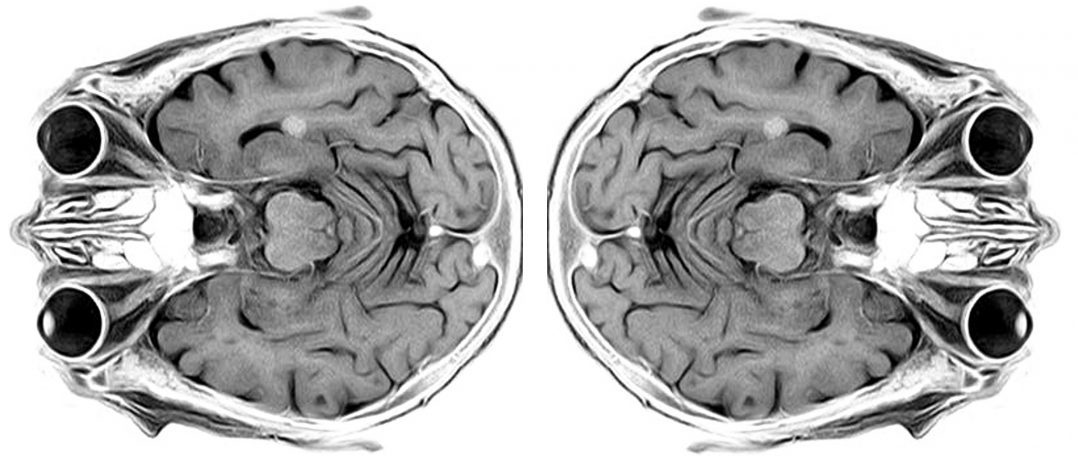

Microglia are the resident immune cells of the brain. Recently researchers conducted single cell analysis of microglia from 10 different species (covering more than 450 million years of evolution). They reported that microglia are only heterogeneous in humans, not other species. They also found that Parkinson’s genes are conserved only in primates (Click here to read more about this).